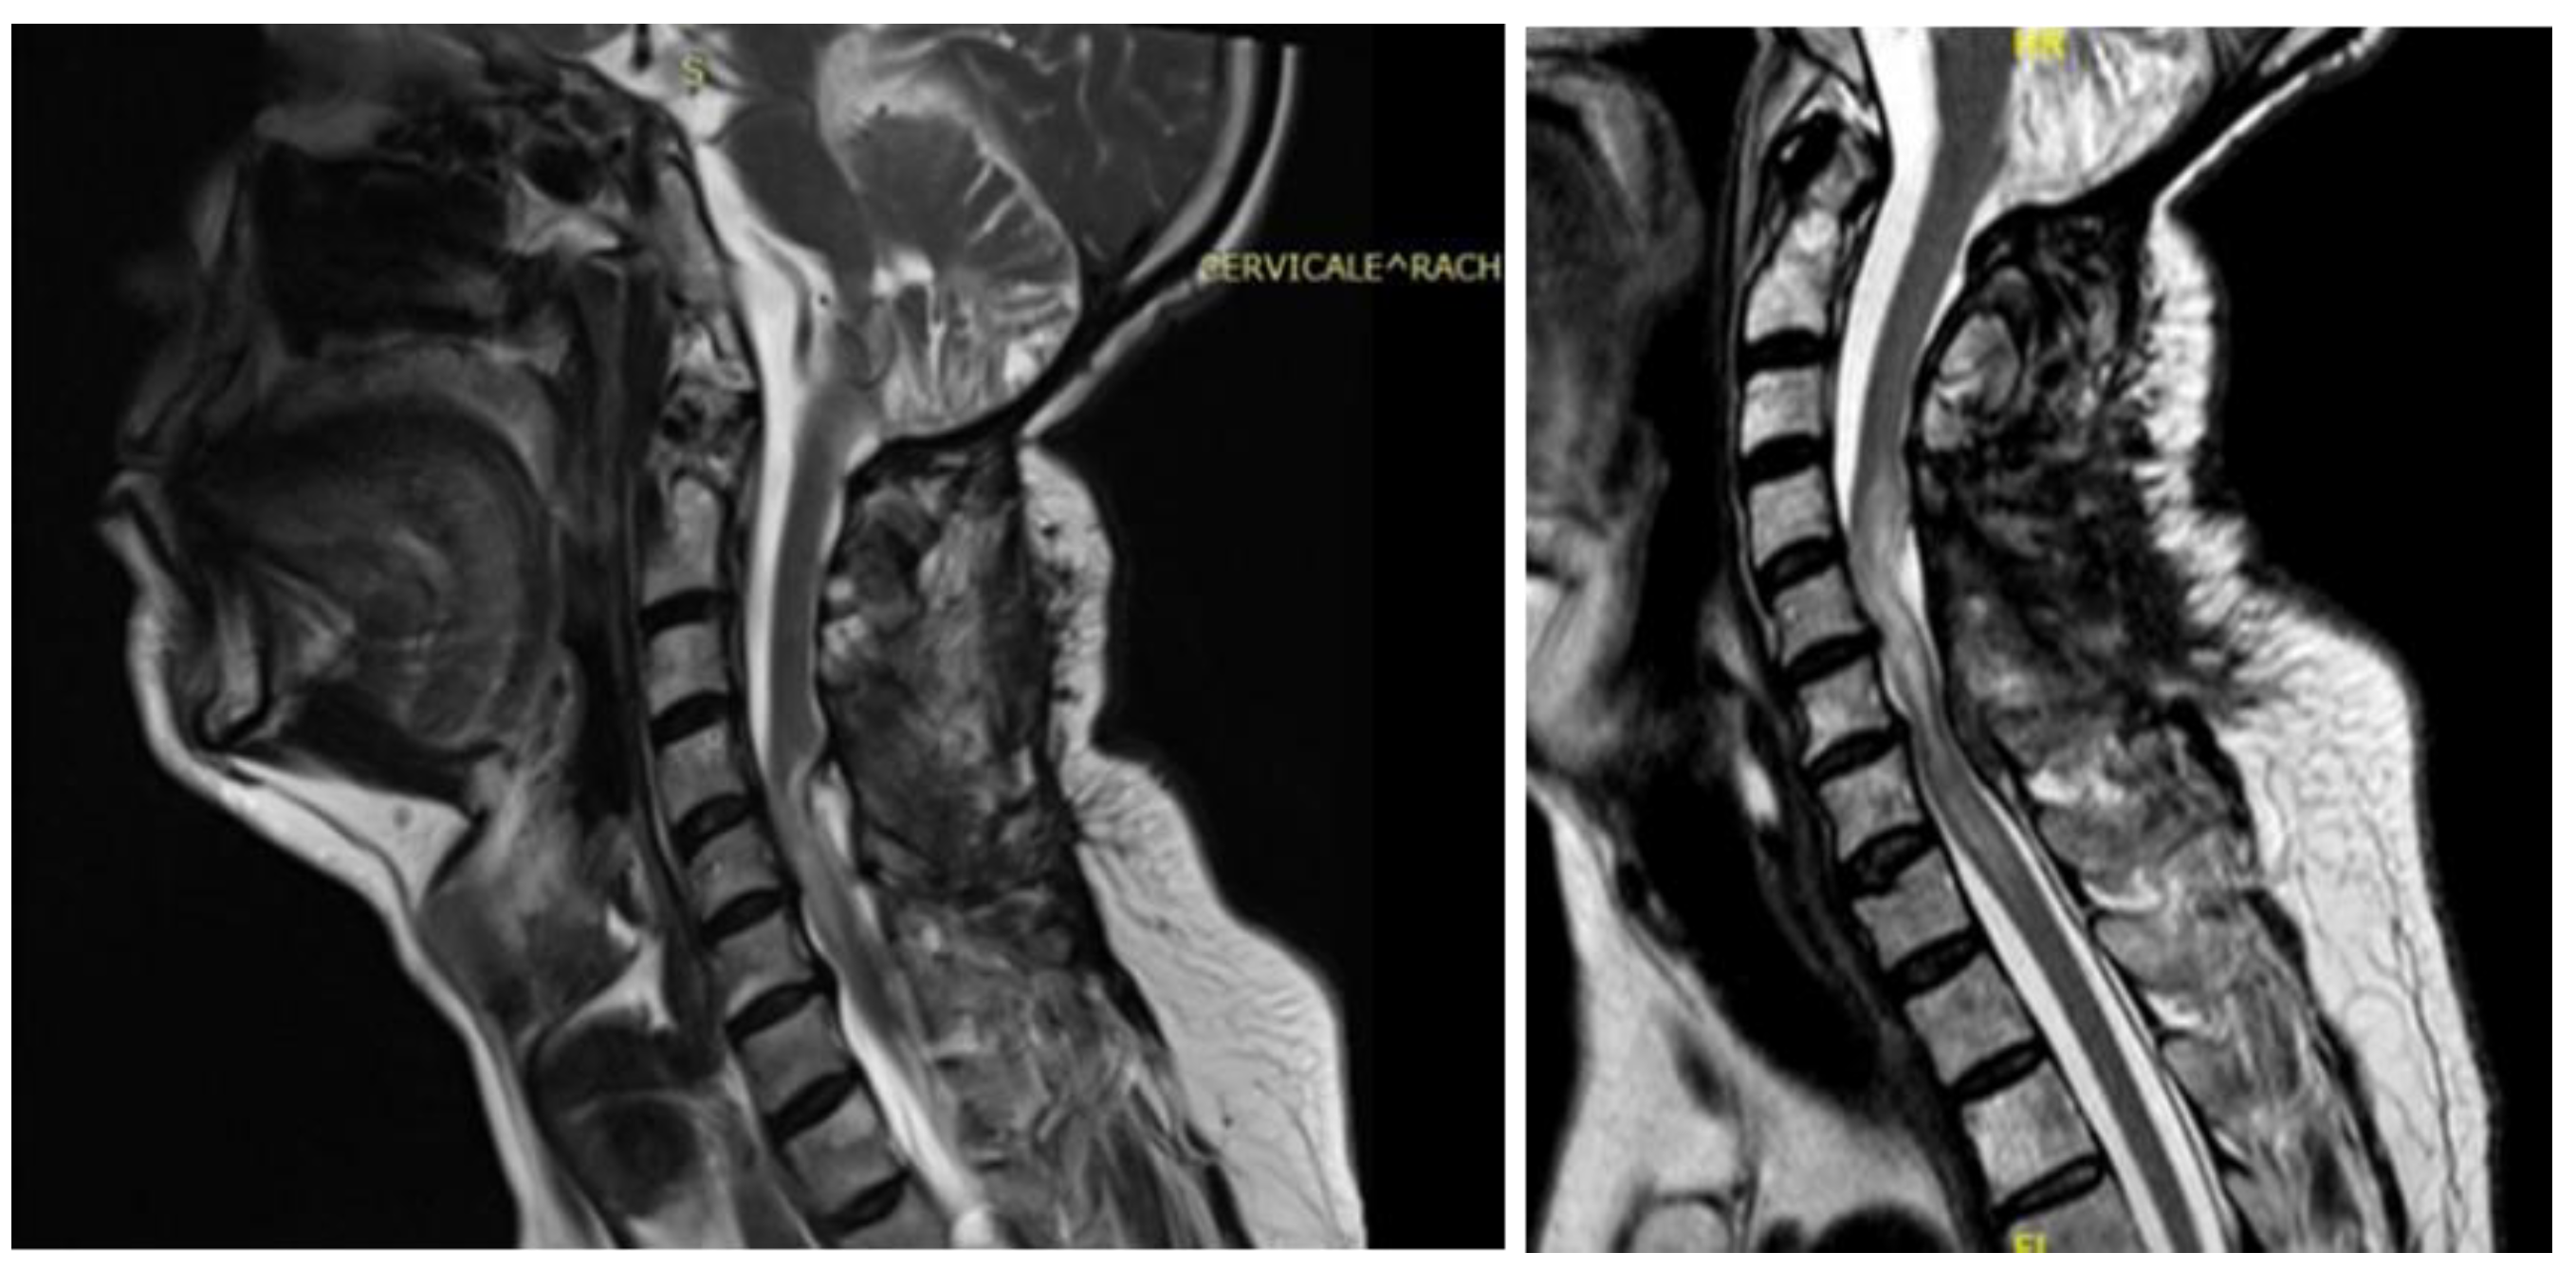

A 62-year-old man, 10 months after surgery for the removal of a spinal cavernoma, developed recurrent left-sided lumbosciatica, paresthesia, hypoesthesia, and an episode of acute urinary retention. Neurological examination revealed weakness in the left lower limb, mild hyperreflexia, and neurogenic bladder. MRI showed an intradural-extramedullary cyst from D3 to D8 and an extradural component from D9 to D11, compressing the spinal cord and causing myelopathy [Figure 4]. The patient underwent a left hemilaminectomy (D6-D10) for cyst removal. Histology confirmed a spinal arachnoid cyst. Postoperatively, the patient remained neurologically stable, the post-operative MRI showed the absence of the anterior cystic collection at the dorsal spine, with only a slight reduction in the area of myelopathy and persistent central spinal cord signal alteration at the D9-10 level [Figure 5]. Eight months later, he experienced worsening of symptoms, including low back pain and paraplegia. The performed MRI revealed a cystic mass from D4 to D8. He underwent a decompressive laminectomy (D5-D10) and cyst fenestration. Postoperative MRI showed resolution of the cyst but an extension of the myelopathic area. Despite these issues, the patient did not experience new neurological deficits over 3 years of follow-up.

Figure 4. Case 3: pre-operative MRI showing an intradural and extradural cyst.

Figure 5. Case 3: post-operative MRI showing the absence of a recurrent cystic formation.